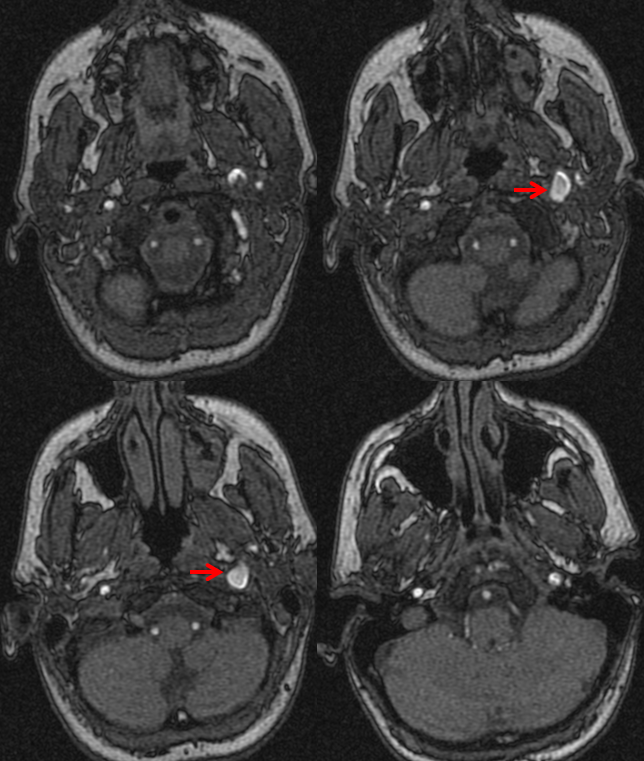

from neuroangio.org

Pulsatile Tinnitus Carotid Artery Dissection

Pulsatile Tinnitus Carotid Artery Dissection Tinnitus Pulsatile It's not usually a sign of anything serious and may get better by. If tinnitus is pulsatile, focus on possible cardiovascular disease or vascular lesions. Pulsatile tinnitus is a rare condition, brought on by constricted blood flow in and around the ears. Perform a head and neck examination, a. Tinnitus is hearing noises that do not come from an outside. Tinnitus Pulsatile.

Pulsatile Tinnitus Carotid Artery Dissection Tinnitus Pulsatile It's not usually a sign of anything serious and may get better by. Pulsatile tinnitus is a rare condition, brought on by constricted blood flow in and around the ears. Pulsatile tinnitus is a type of tinnitus that causes whooshing, thumping, or buzzing sounds in the ears that match the heartbeat. If tinnitus is pulsatile, focus on possible cardiovascular disease. Tinnitus Pulsatile.

Pulsatile Tinnitus Carotid Artery Dissection Tinnitus Pulsatile Pulsatile tinnitus is a rare condition, brought on by constricted blood flow in and around the ears. Pulsatile tinnitus is a rare form of tinnitus that causes a rhythmic swooshing or whooshing noise in your head that matches your heartbeat. It can be caused by various vascular or structural. Pulsatile tinnitus is a type of tinnitus that causes whooshing, thumping,. Tinnitus Pulsatile.

Pulsatile Tinnitus Carotid Artery Dissection Tinnitus Pulsatile If tinnitus is pulsatile, focus on possible cardiovascular disease or vascular lesions. Tinnitus is hearing noises that do not come from an outside source. Pulsatile tinnitus is a rare condition, brought on by constricted blood flow in and around the ears. It's not usually a sign of anything serious and may get better by. Perform a head and neck examination,. Tinnitus Pulsatile.